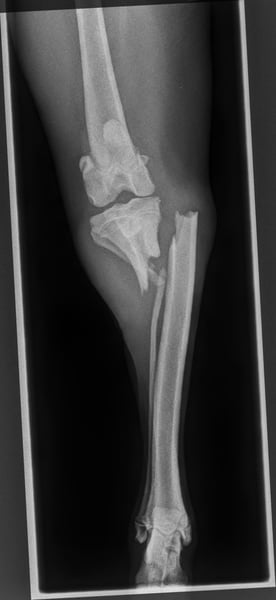

Juno wurde als etwa 7-monatiger Welpe in einem Tierheim auf Kreta abgegeben, in dem wir gerade im Einsatz waren. Zu der Zeit hatte er zwei gelähmte Hintergliedmaßen durch eine Rückenmarksverletzung und einen Knochenbruch am linken Schienbein. Er muss kurz zuvor einen schweren Unfall gehabt haben und hatte zumindest einen kleinen Schutzengel, der ihn uns kurz vor unserer Abfahrt in die Arme leitete.

Durch seinen Unfall und den verwachsenen Knochenbruch hat Juno ein leichtes motorisches Defizit in der Hinterhand behalten, er sollte vorerst nur moderat bewegt werden und braucht dafür hundegerechte Auslastung für's Köpfchen und ganz viel Streicheleinheiten. Als Jagdhund-Mischling ist bei ihm ein Interesse an Wildspuren vorhanden, hierauf muss bei den Spaziergängen und im Training eingegangen werden.